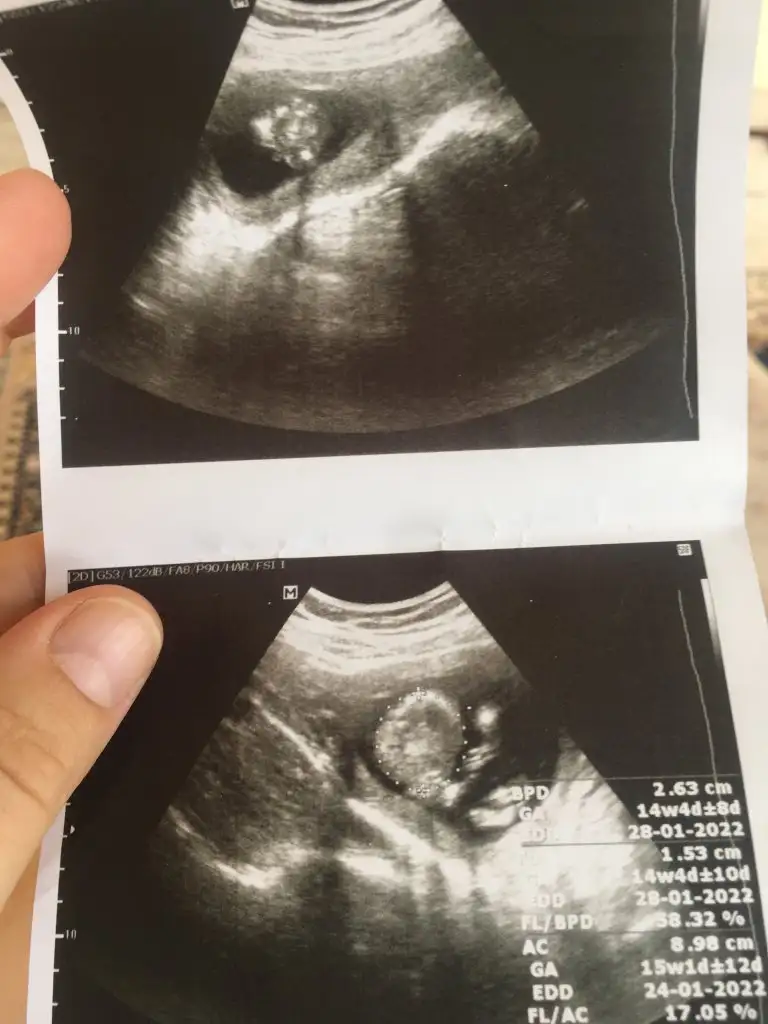

Merhaba teyzeleri 13 haftalık oldu çok şükür cinsiyet tahmini yapar mısınız ? 😇 Bir kaç kişiye sordum genelde herkes aynı tahmini yaptı tabi ki en önemlisi hayırlı ve sağlıklı bir evlat olması ama insan cinsiyeti öğrenene kadar merakta ediyor sizin de tahminlerinizi almak istedim 😊

Erkek 💙

Benimkide 12 haftalık sizce erkekmi kızmı ? ☺️